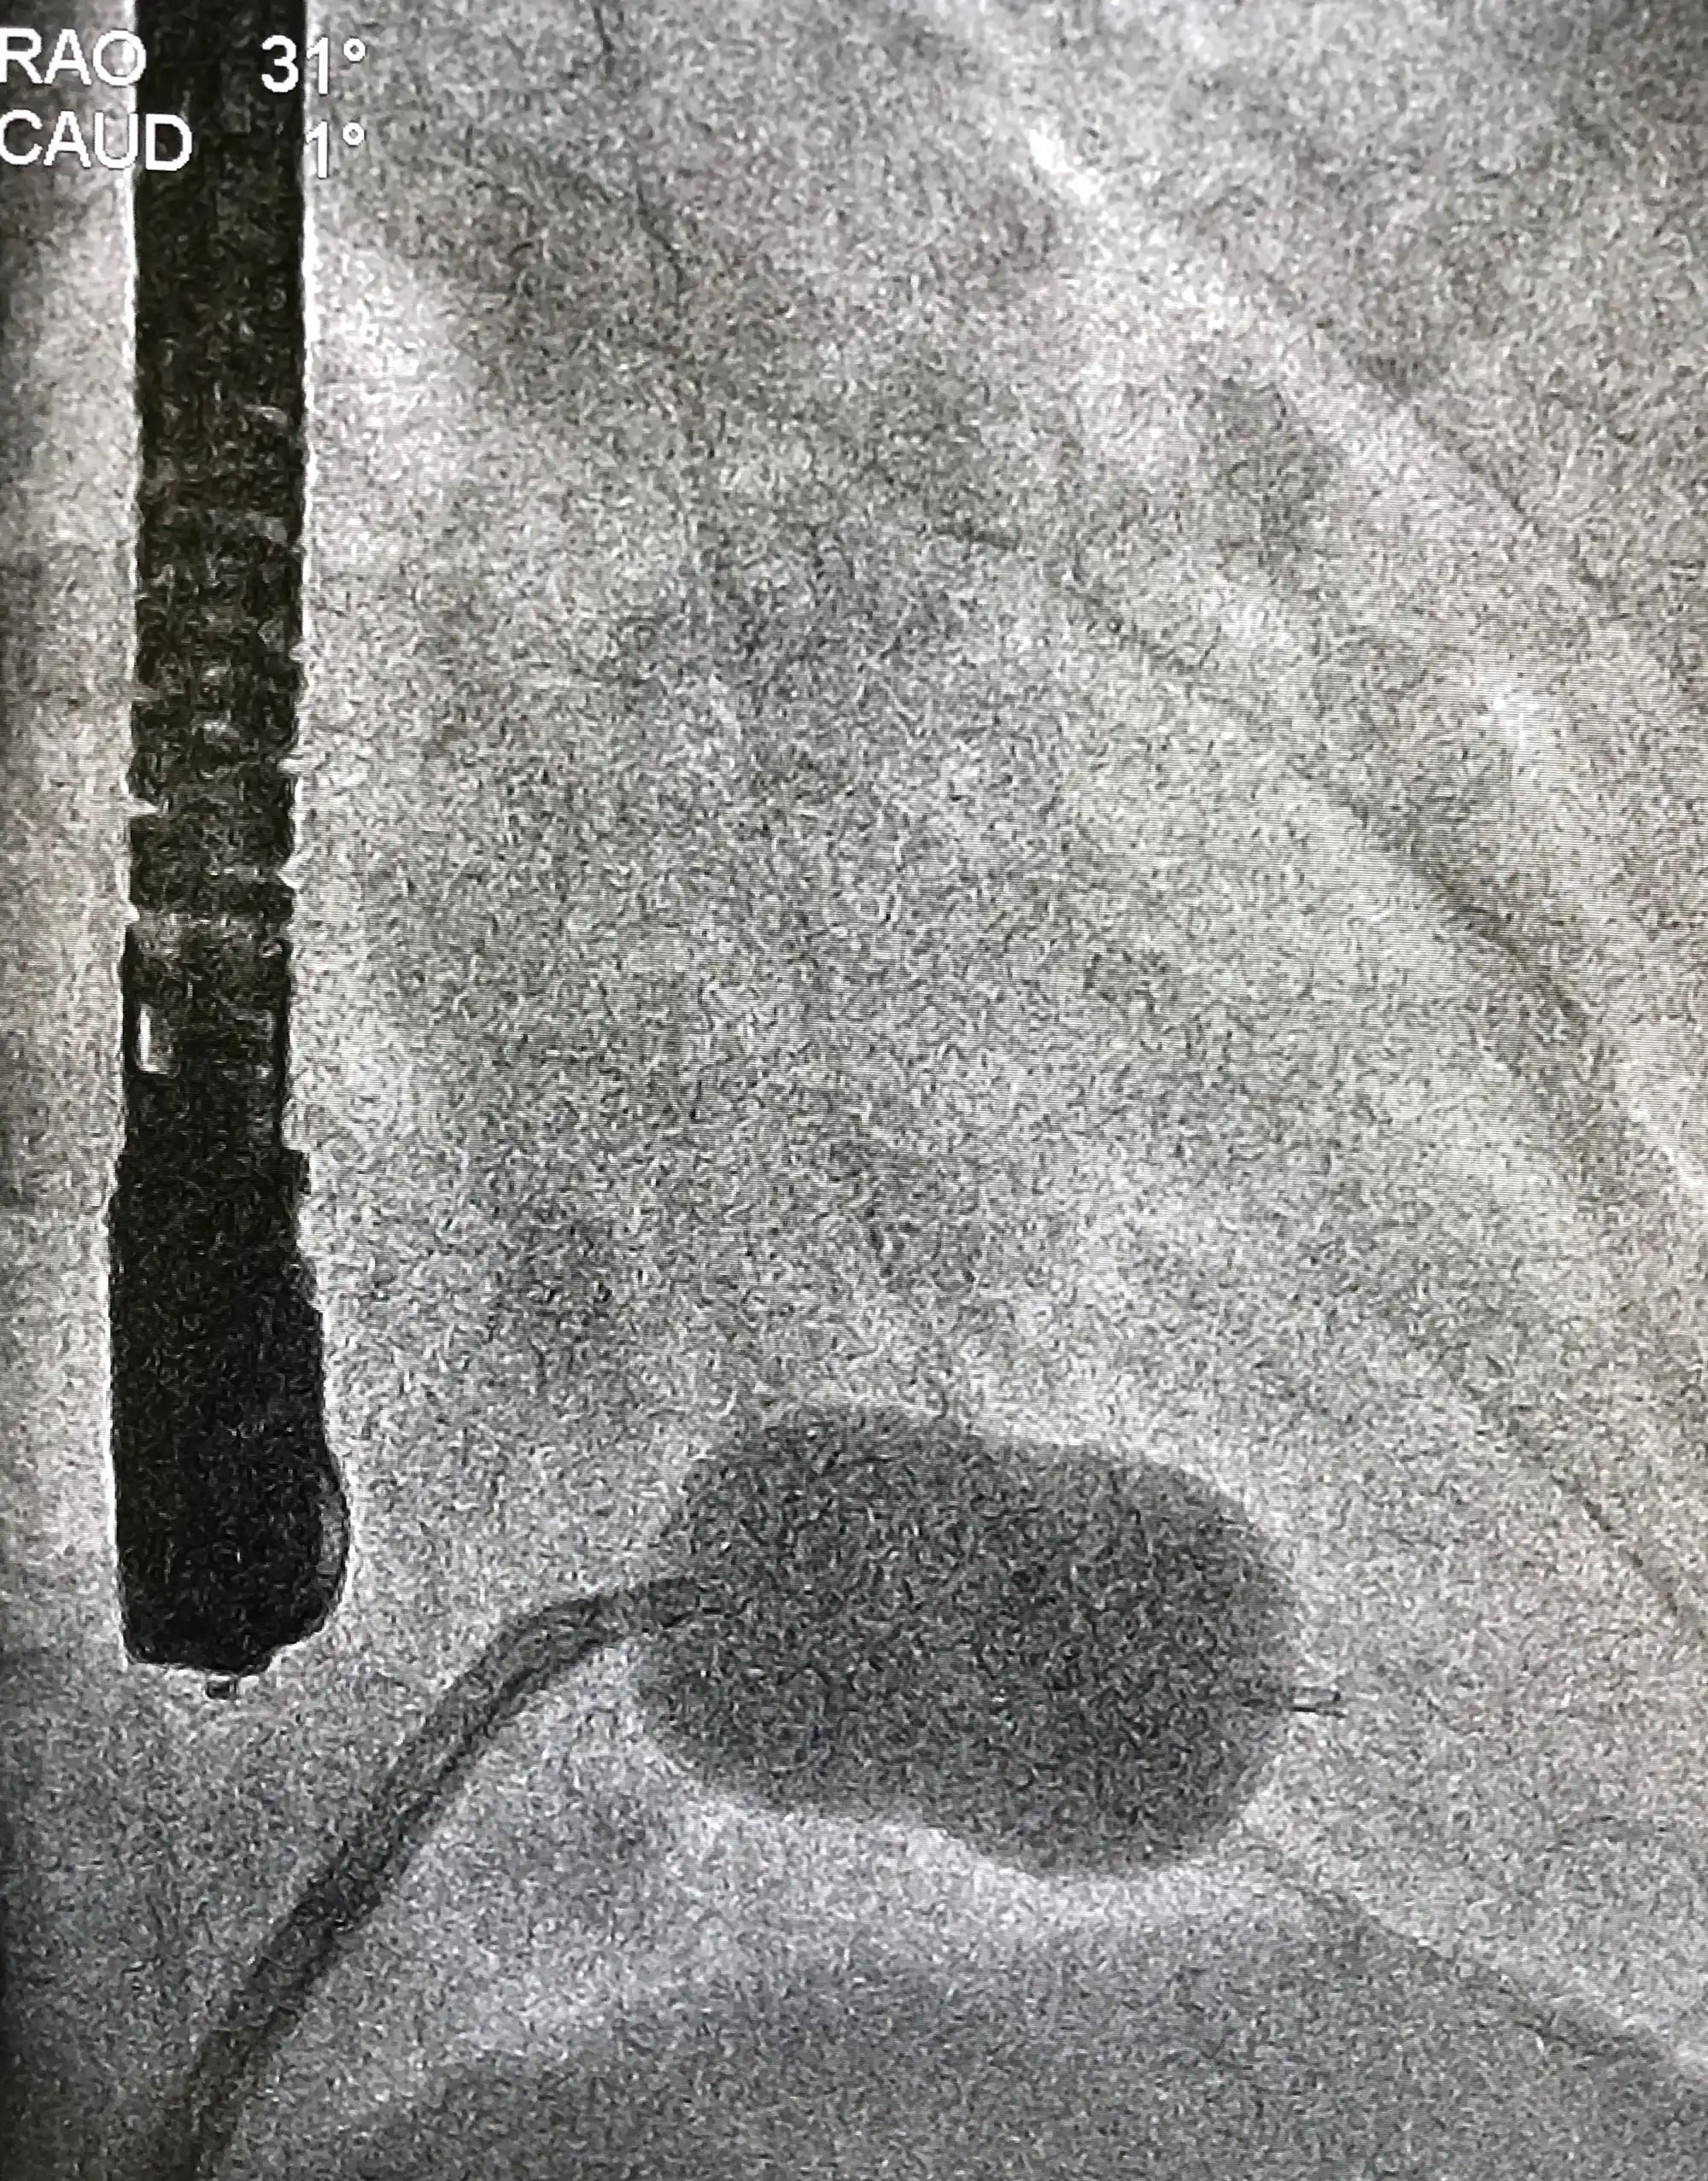

Coronary Angiography

In an angiogram, X-rays are used to determine whether plaque has blocked the blood vessels. During this test, which requires local anesthesia, a doctor makes a small incision in the skin near the groin, inserts a thin tube called a catheter, and guides it into an artery. The doctor moves the catheter to the area to be examined and injects a dye that highlights any narrow, enlarged, or blocked blood vessels.